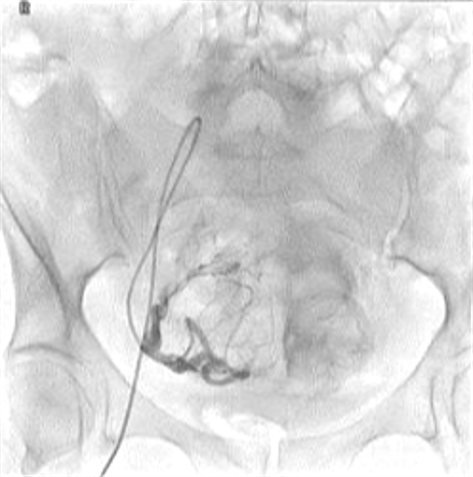

所有年龄超过 40 岁的患者, 卵巢受损 14%-43% 研究中闭经发生率(15%)与单纯UAE报告相似,可能与患者年龄(≥45岁)及卵巢储备自然下降有关。 ![]() 50岁,长期因子宫肌瘤导致月经出血过多,痛经和贫血。 子宫肌瘤栓塞术前,显示双侧子宫动脉发育不全,子宫肌瘤双侧卵巢动脉。 经皮股动脉穿刺双侧卵巢动脉栓塞,先500μm-700μm emboSphere 微球 术后4周,和6月的中短期随访,月经正常,子宫容积减少,贫血纠正,无卵巢功能衰竭。但看起来非灌注容积较少。 术后9月,由于子宫肌瘤持续存在,患者自己希望绝经,行全子宫和双侧卵巢切除术 术后病理,子宫内可见栓塞微粒伴有坏死,卵巢内也见栓塞微粒,但卵巢功能未受损。